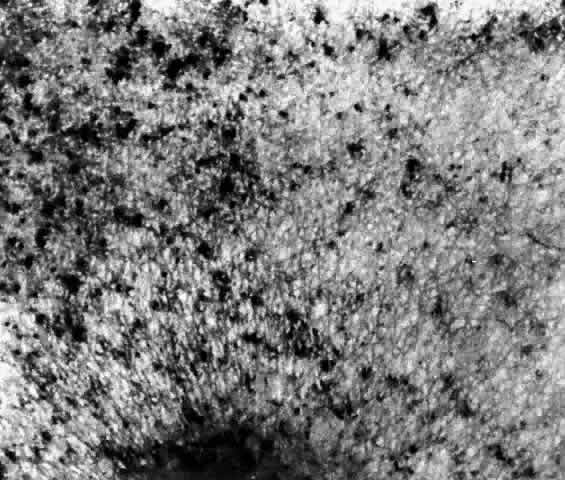

These deposits are strongly birefringent, and striking macular birefringence may be readily visualized in sections of the retina (Fig. 5) even in the unstained state as well as when lightly stained with cresyl violet or sudanophilic dyes.8 Loss of the ganglion cells and atrophy of the optic nerve, which is also evident, are accompanied by a thinning of the nerve fiber layer.

Histochemical stains have characterized the retinal lipid as a glycolipid,7 and lipid chromatography of retinal cells shows a prominent spot of GM2-ganglioside.9